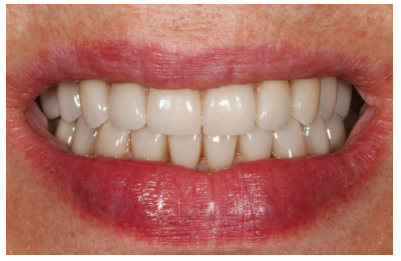

Cuatro meses después se procede a la carga de los implantes insertados en esta segunda fase quirúrgica. De nuevo se opta por unas segundas prótesis provisionales de carga progresiva, elaboradas del mismo modo que las anteriores Tres meses después la oclusión está preparada para la confección de la prótesis definitiva, por lo que se transforma la prótesis en una prótesis metal-cerámica, atornillada sobre transepitelial confeccionada mediante cad-cam (Figuras 25-26). La paciente ha recuperado la función demandada, así como la corrección de la oclusión de la prótesis completa, que presentaba una mordida cruzada lateral derecha con disminución de la dimensión vertical al inicio del tratamiento. La paciente acude a sus revisiones y el tratamiento se mantiene estable tal como se muestra en las imágenes tomadas a los 10 años de seguimiento (Figuras 27-28).